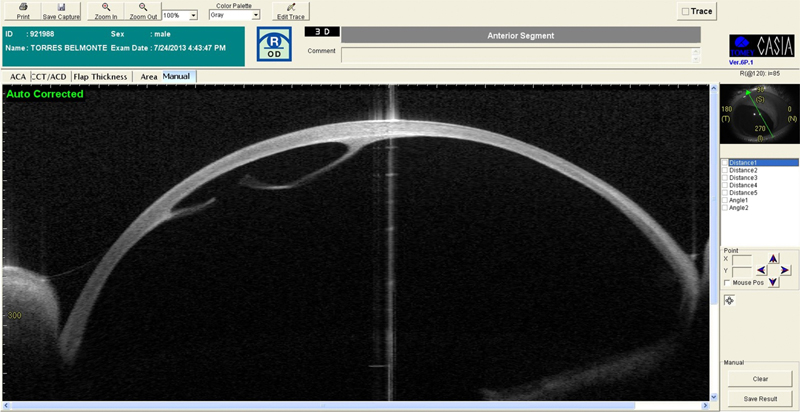

Se le realizó una OCT de polo anterior donde se ratificó la rotura de la membrana de Descemet del OD y la sinequia iridocorneal del OI (

Figura 3 y

Figura 4).

Figura 3. Visante de OD con rotura de la membrana de Descmeet.

Figura 4. Visante del OI con sinequia anterior.